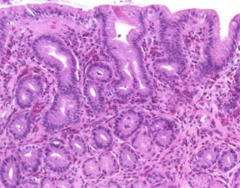

Chronic Enteritis

Front

Back